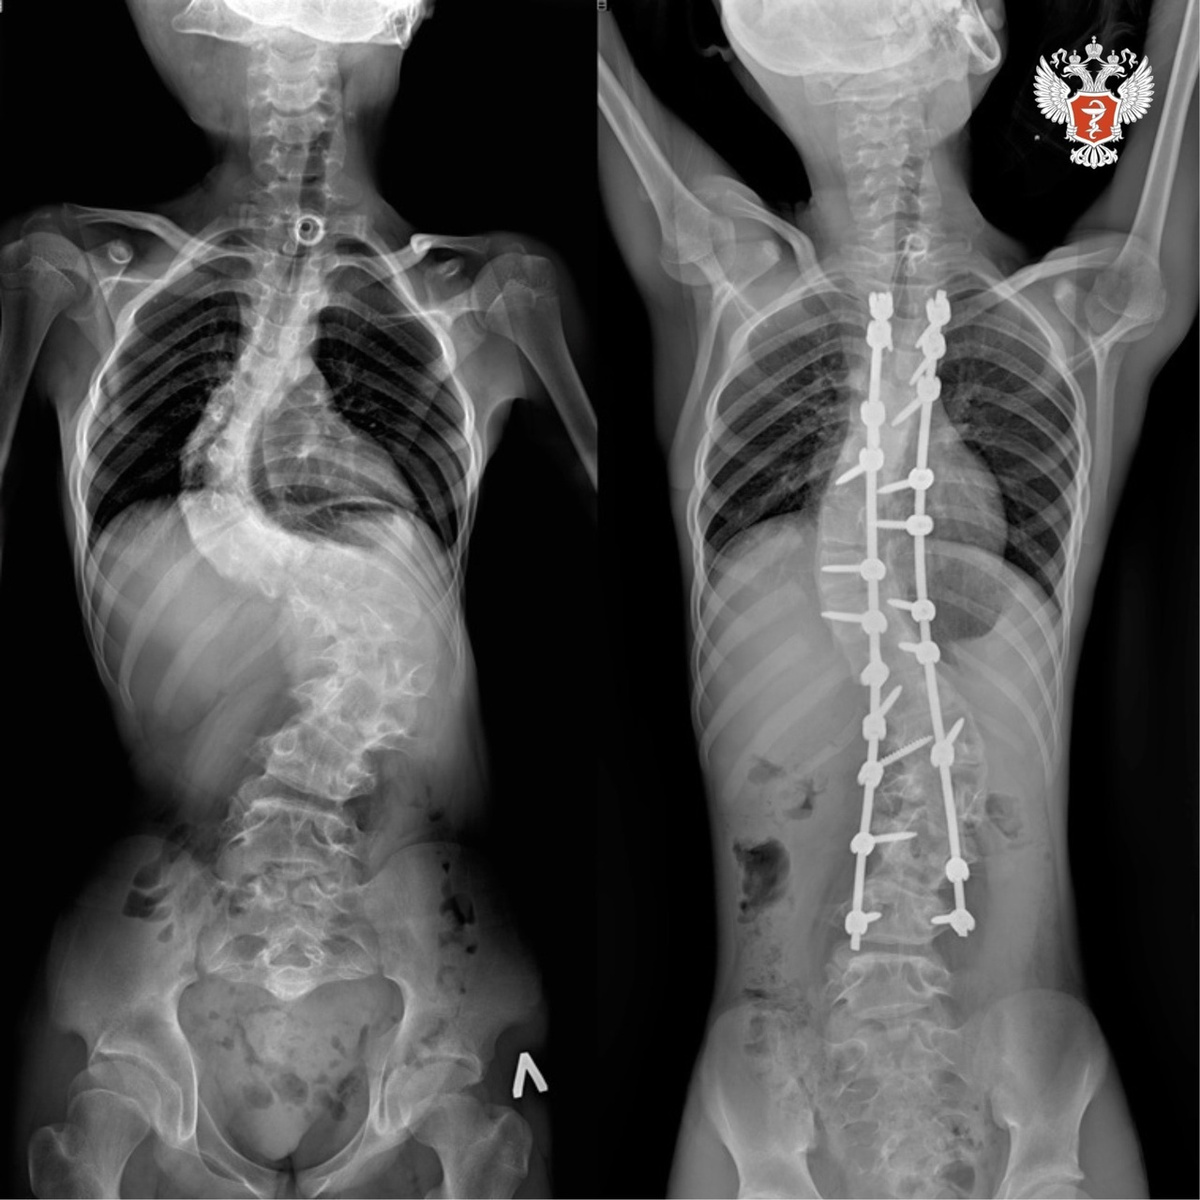

Операция Позвоночника Фото

Операция Позвоночника Фото 115 фото